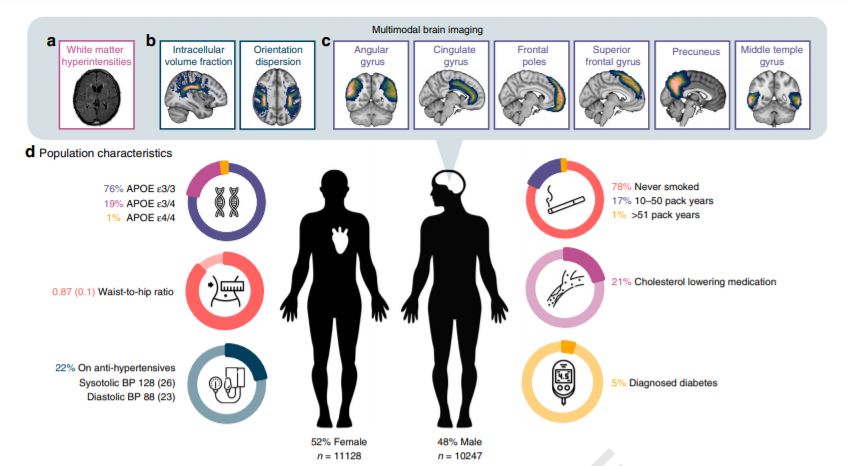

El equipo de investigación analizó escáneres cerebrales por resonancia magnética de más de 22.000 participantes del Biobanco del Reino Unido , buscando cambios en las vías de la materia gris y la materia blanca del cerebro, además de registrar los datos clínicos, demográficos y cognitivos de los voluntarios.

El equipo comparó los datos de la resonancia magnética con los datos cognitivos y clínicos, y encontró que en los participantes de entre 44 y 70 años, la presión arterial más alta se relacionó con un rendimiento cognitivo más bajo. Curiosamente, los adultos mayores (los mayores de 70 años) no mostraron el mismo efecto.

Aunque solo el 5 por ciento de los inscritos en el estudio tenían un diagnóstico de diabetes tipo 2, ese estado también predijo una función ejecutiva más baja.